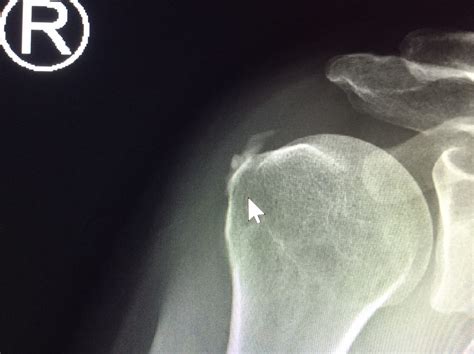

To confirm the diagnosis of calcium deposits in shoulder, an orthopedic specialist will usually conduct a physical examination followed by imaging tests. Because these deposits are essentially mineral structures, they show up very clearly on standard medical imaging.

X-ray The most common tool; clearly shows the shape and size of the calcium deposit.